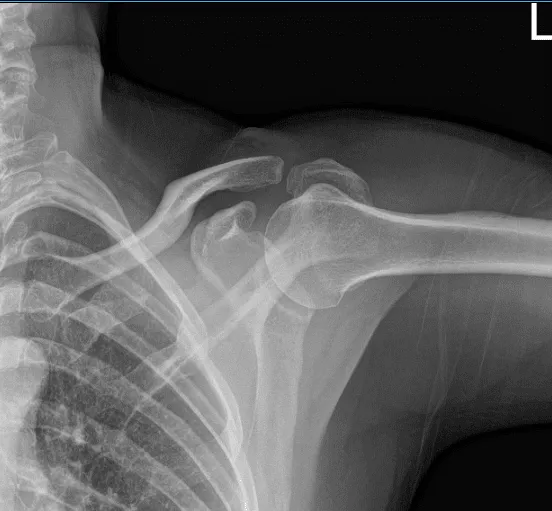

He is here with an X-ray of the left shoulder. He is left hand dominant. He is not able to work due to pain. He has tried stretching at home, and Tylenol to no benefit.

His X-ray showed normal left shoulder radiographs so we decided to get an MRI to see the reason for the pain.